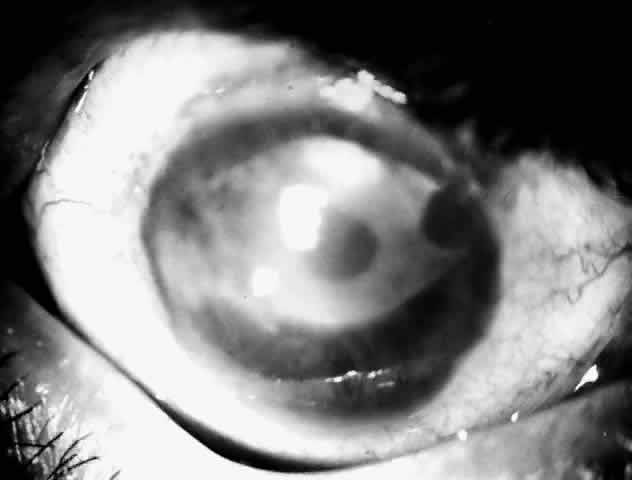

Acanthamoeba infection of the cornea is being reported with increasing frequency. While this is associated with contact lens wear in industrialized countries, in developing countries it is almost exclusively seen in non-contact lens wearers (Fig. 4).6 Misdiagnosis and inappropriate treatment are common.

Fig. 4. Typical ring infiltrate in a case of Acanthamoeba keratitis in a non-contact lens wearer.